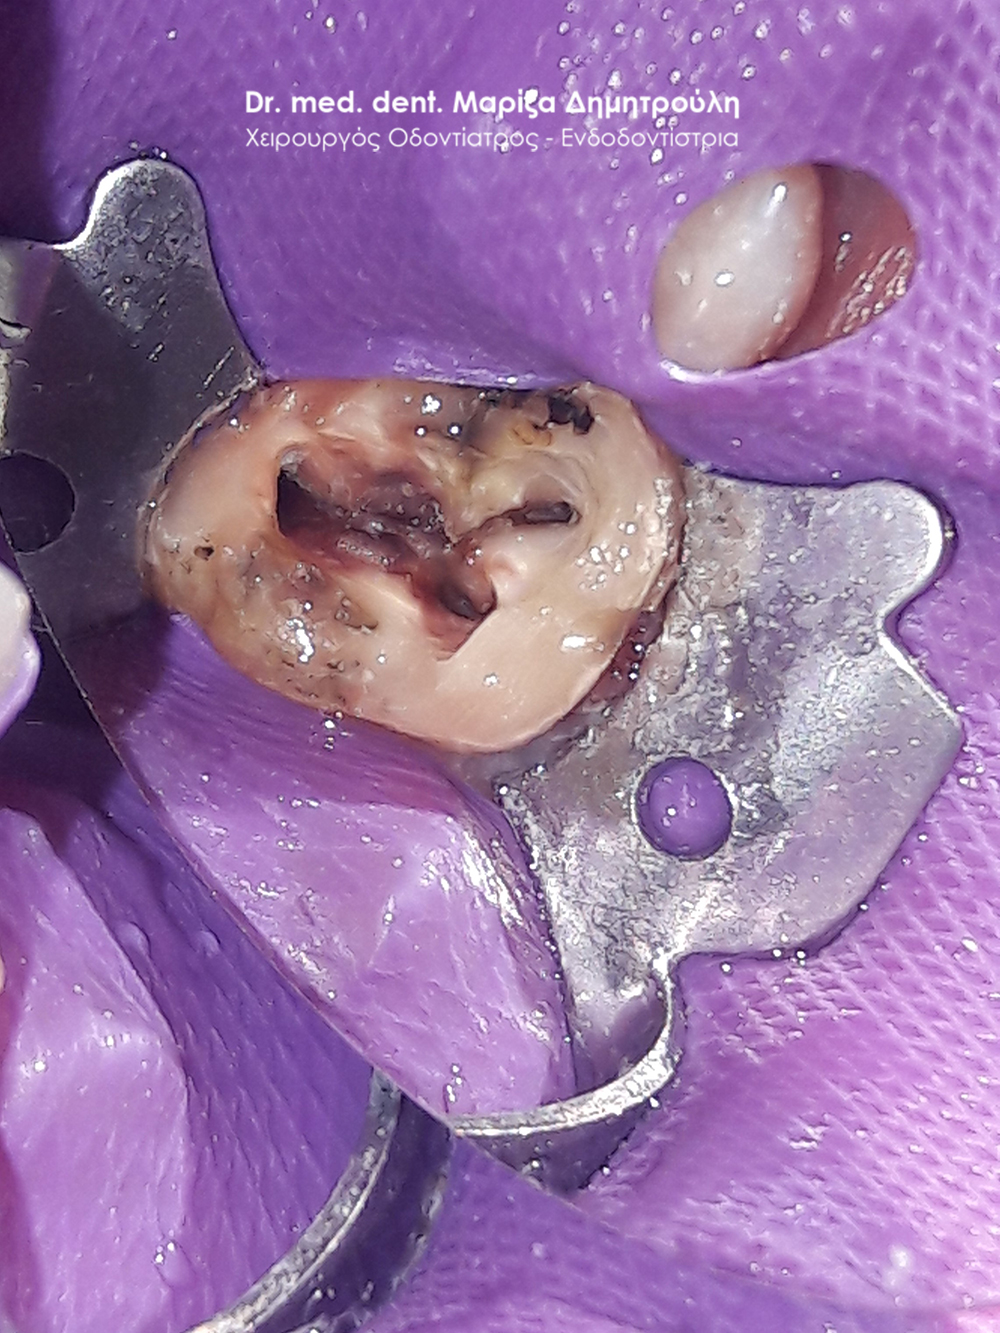

Pus after opening the tooth

Clinical photo of root canal filling